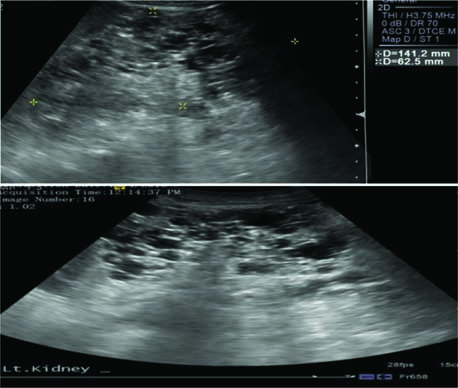

The primary methods to diagnose the presence of AMLs are imaging technology, ultrasound (US), and magnetic resonance imaging (MRI) in the abdominal region (65). An example of a positive image is shown in Figure 2. However, cautious interpretation is warranted when considering these US data, as US often cannot detect fat-poor angiomyolipomata, with approximately a third of patients demonstrating fat-poor lesions. Continued monitoring of renal AMLs is crucial, as they exhibit continued growth and patients may develop aneurysms as the AMLs enlarge. Increased size also leads to an increased risk of bleeding; AMLs > 3 cm and aneurysms ≥ 5 mm are associated with an increased risk of severe bleeding (61).

Figure 2: Contrast enhanced CT images of abdomen in axial (a) and coronal (b) planes. This is the case of a 16-year-old female with tuberous sclerosis undergoing treatment with everolimus. The CT scan shows right heminephrectomy and an enlarged left kidney with multiple cysts and angiomyolipomas.